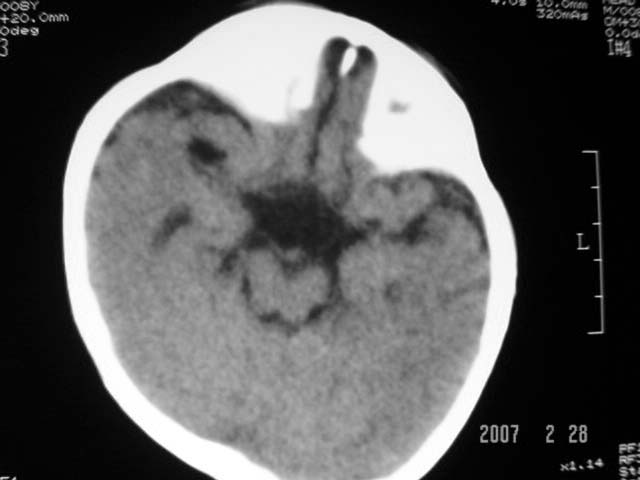

标题: PED0015:男,8M,发现不会坐立及神情异常,前囟已闭,双眼斜视,

脑回较深,白质范围小,灰白质比例失调。余未见明显异常。

考虑:脑白质发育不良,必要时请做mri进一步检查。